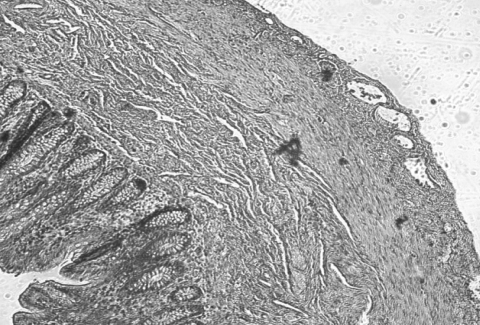

Un'ecografia

addominale conferma un diffuso ispessimento della parete

intestinale e la presenza di una piccola falda ascitica.

(fig.1-2)